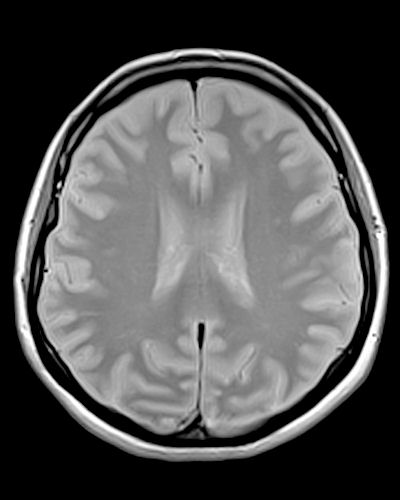

Brain MRI without abnormalities